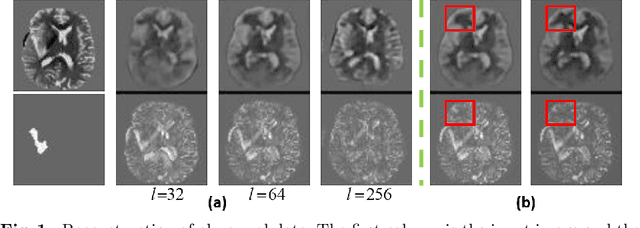

Abstract:Variational Auto-Encoders (VAEs) have shown great potential in the unsupervised learning of data distributions. An VAE trained on normal images is expected to only be able to reconstruct normal images, allowing the localization of anomalous pixels in an image via manipulating information within the VAE ELBO loss. The ELBO consists of KL divergence loss (image-wise) and reconstruction loss (pixel-wise). It is natural and straightforward to use the later as the predictor. However, usually local anomaly added to a normal image can deteriorate the whole reconstructed image, causing segmentation using only naive pixel errors not accurate. Energy based projection was proposed to increase the reconstruction accuracy of normal regions/pixels, which achieved the state-of-the-art localization accuracy on simple natural images. Another possible predictors are ELBO and its components gradients with respect to each pixels. Previous work claimed that KL gradient is a robust predictor. In this paper, we argue that the energy based projection in medical imaging is not as useful as on natural images. Moreover, we observe that the robustness of KL gradient predictor totally depends on the setting of the VAE and dataset. We also explored the effect of the weight of KL loss within beta-VAE and predictor ensemble in anomaly localization.